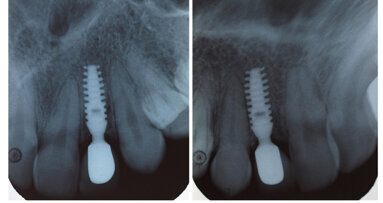

1. Повърхността на импланта: избирайте импланти с микротопография и биоактивна повърхност, която помага на контакта с костта, и такива с макротопография (цялостна форма), стабилизираща костния профил с малко или никаква загуба на крестална кост.

2. Връзки с абатмънта: вътрешните връзки имат опростено поставяне на абатмънта. Ако се остави разстояние от ръба на комплекса имплант–абатмънт от външната повърхност на импланта, ще се образува зона на свързваща тъкан. Резултатът е по-добро запазване на костта. Абатмънтите трябва да бъдат поставяни посредством специално изработени винтове, които да осигуряват стабилност в дългосрочен план.

5. По-ранна остеоинтеграция и възстановителна фаза: усъвършенстваните имплантни повърхности и форми способстват за първичната стабилност в костта и подобряват остеоинтеграцията. Ранното натоварване на импланта става все по-изпълнимо, но избирайте случаите внимателно.

6. Мениджмънт на меките и твърдите тъкани: навременното поставяне на временните импланти може да повлияе на опората и контура на тъканта. Напредъкът при костните графтове и запазването на тъканта помага да се запазят меките тъкани, да се поддържа контурът на анатомичната кост и да се подобри гингивалната естетика.